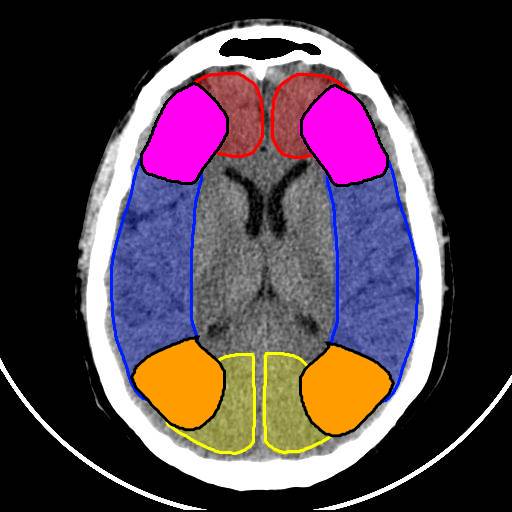

Territoires vasculaires

Territoire jonctionnel antérieur et postérieur